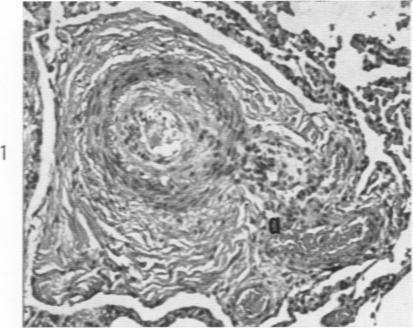

Hypertension of the pulmonary circulation due to congenital glomoid obstruction of the pulmonary arteries.

Am J Pathol. 1961 Jul;39(1):75-93.